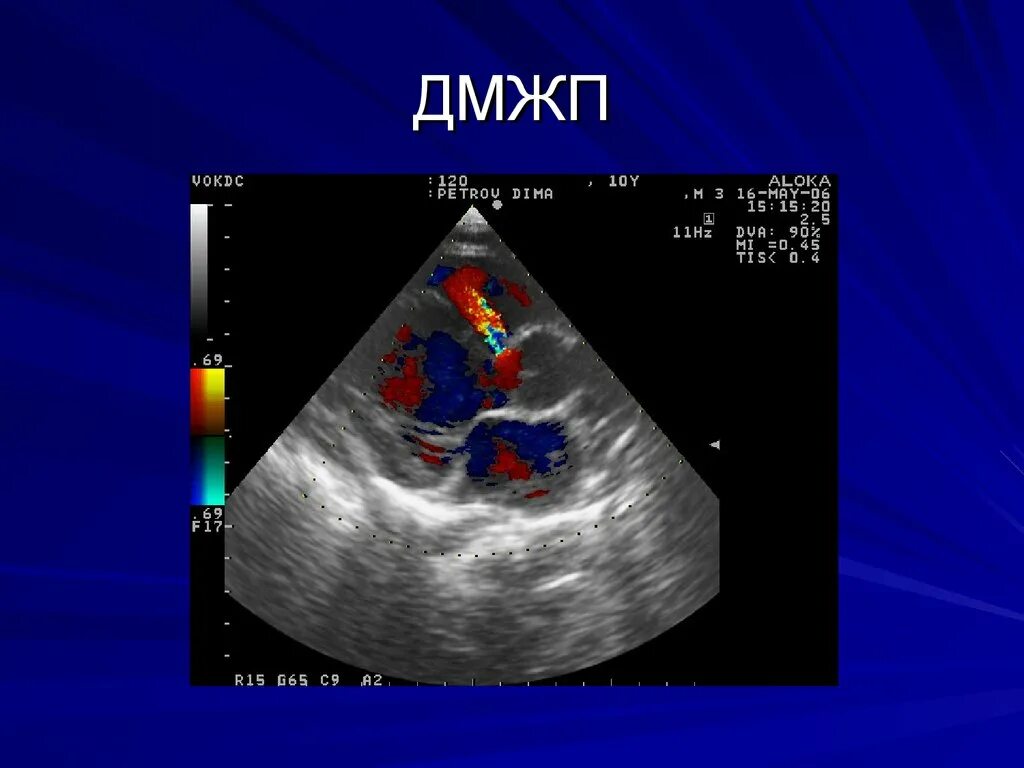

Впс дмжп у детей